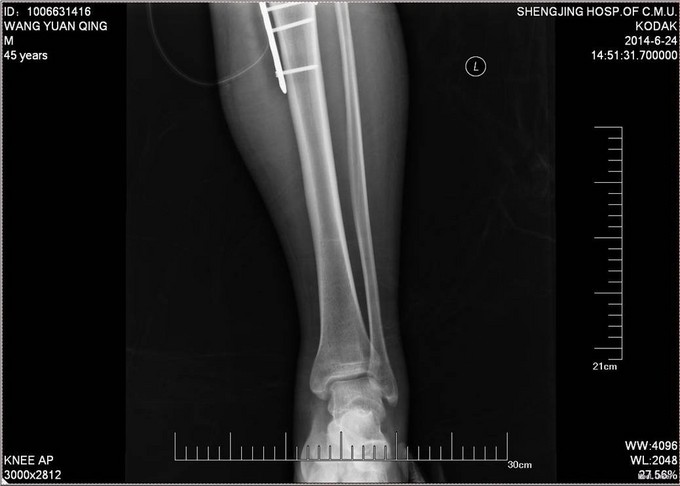

患者自诉于2014-6-1中午骑摩托车被汽车撞翻,伤后昏迷,被肇事司机寄送到当地医院,拍片检查,诊断为:颅脑损伤,脾破裂,左股骨骨折,左胫骨平台骨折。给予保守治疗,并转往盖州市中心医院,急诊下行脾切除术,右下肢给予石膏固定,待患者病情稳定后建议转往上级医院。现患者为求进一步诊治来我院就诊,以“左股骨骨折,左胫骨平台骨折,颅脑损伤,脾切除术后”为主要诊断收入我科。患者伤来无恶心呕吐,腹痛腹胀,胸闷心悸等特殊不适,饮食差、睡眠可,小便可,未大便,体重无明显变化。

诊断:左股骨骨折,左胫骨平台骨折 双侧胸腔积液 脑出血 脾切除术后 患者入院后见患肢肿胀明显,给予患肢抬高位,冷敷,甘露醇消肿等对症治疗,带患肢出现褶皱试验阳性后,全麻下行右股骨干骨折闭合复位髓内针固定术;左胫骨平台骨折切口复位钢板内固定术,术后患者肿胀明显,给予抗炎,消肿,冷敷,患肢抬高等对症治疗。患者每天换药观察切口愈合情况,无红肿及渗出,待伤口14天后予以拆线治疗,予以出院,给予康复处方。